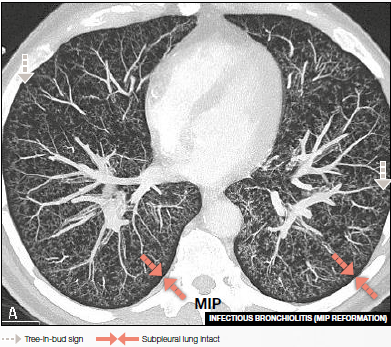

Branching Centrilobular Micronodulations (Tree-in-Bud Pattern) of Bronchiolar origin are associated with different conditions

• Infectious bronchiolitis

Axial MIP image shows tree-in-bud pattern in a bilateral distribution.